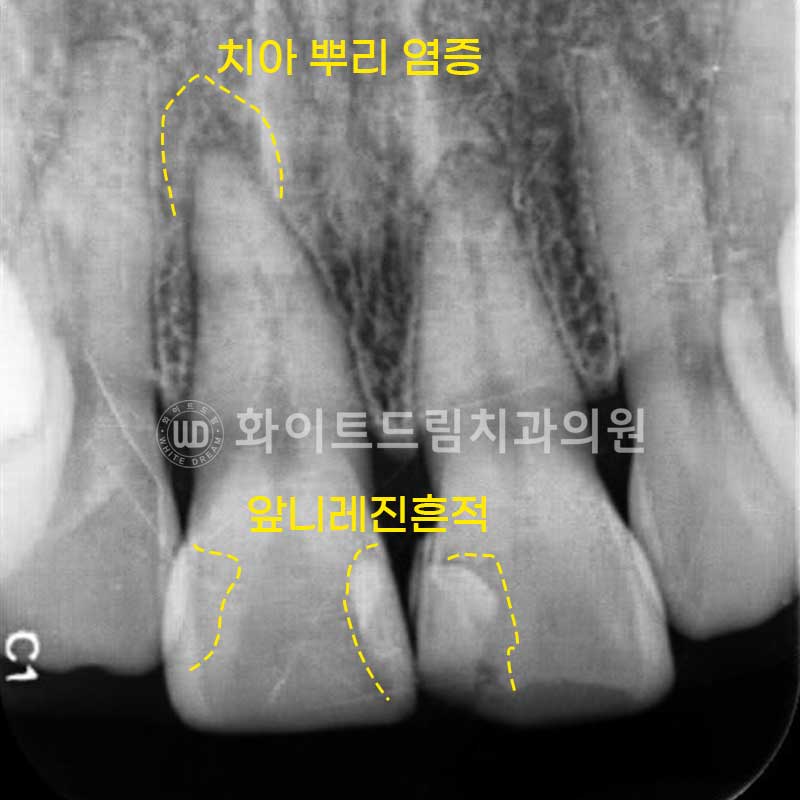

▲ 신논현라미네이트 치료 전 구내 사진, 치경부 충치 & 앞니 레진이 노후된 상태. (25.02.11)

진단 및 확인하기 위해 X-RAY 사진을 촬영해 보았습니다.

치경부 충치가 깊게 있는 11번 앞니는 이 충치로 인해

치아 뿌리 염증까지 발생한 상태였습니다.